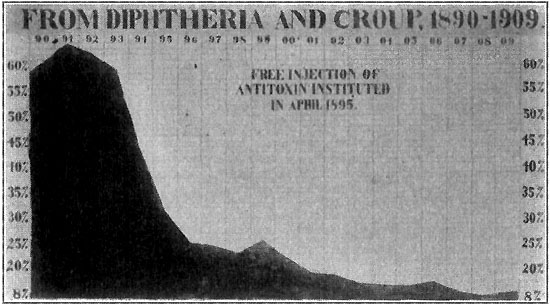

294 Death-Rate from Diphtheria and Croup